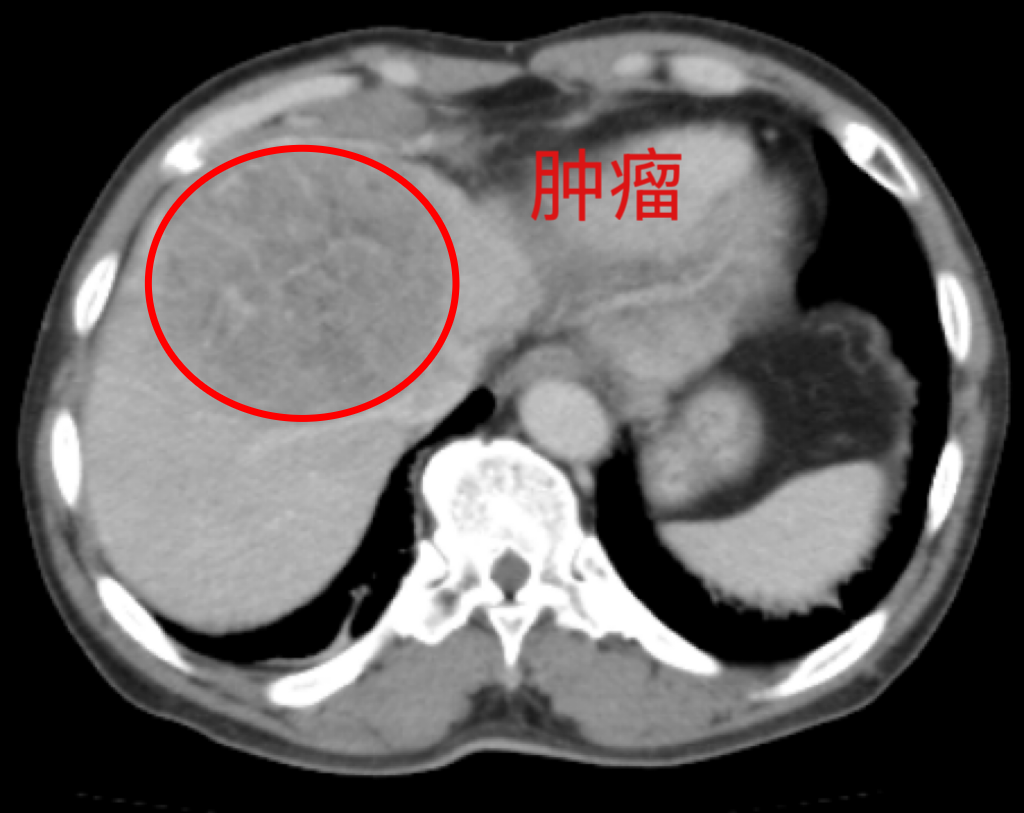

一个月前,63岁的李大爷因突发腹痛到当地医院就诊,CT检查结果显示肝脏占位性病变。经过进一步检查,被确诊为原发性肝癌。“肝癌”两个字如晴天霹雳,让李大爷一家人陷入恐慌,在朋友的介绍下转入该院肝胆外科。

(术前影像检查)

肝癌是严重威胁患者生命和健康的恶性肿瘤。外科手术是肝癌的主要治疗方式,原发性肝癌手术难度大、风险高,尤其对高龄患者而言,对手术团队的技术、围术期管理及术后康复均提出极高要求。